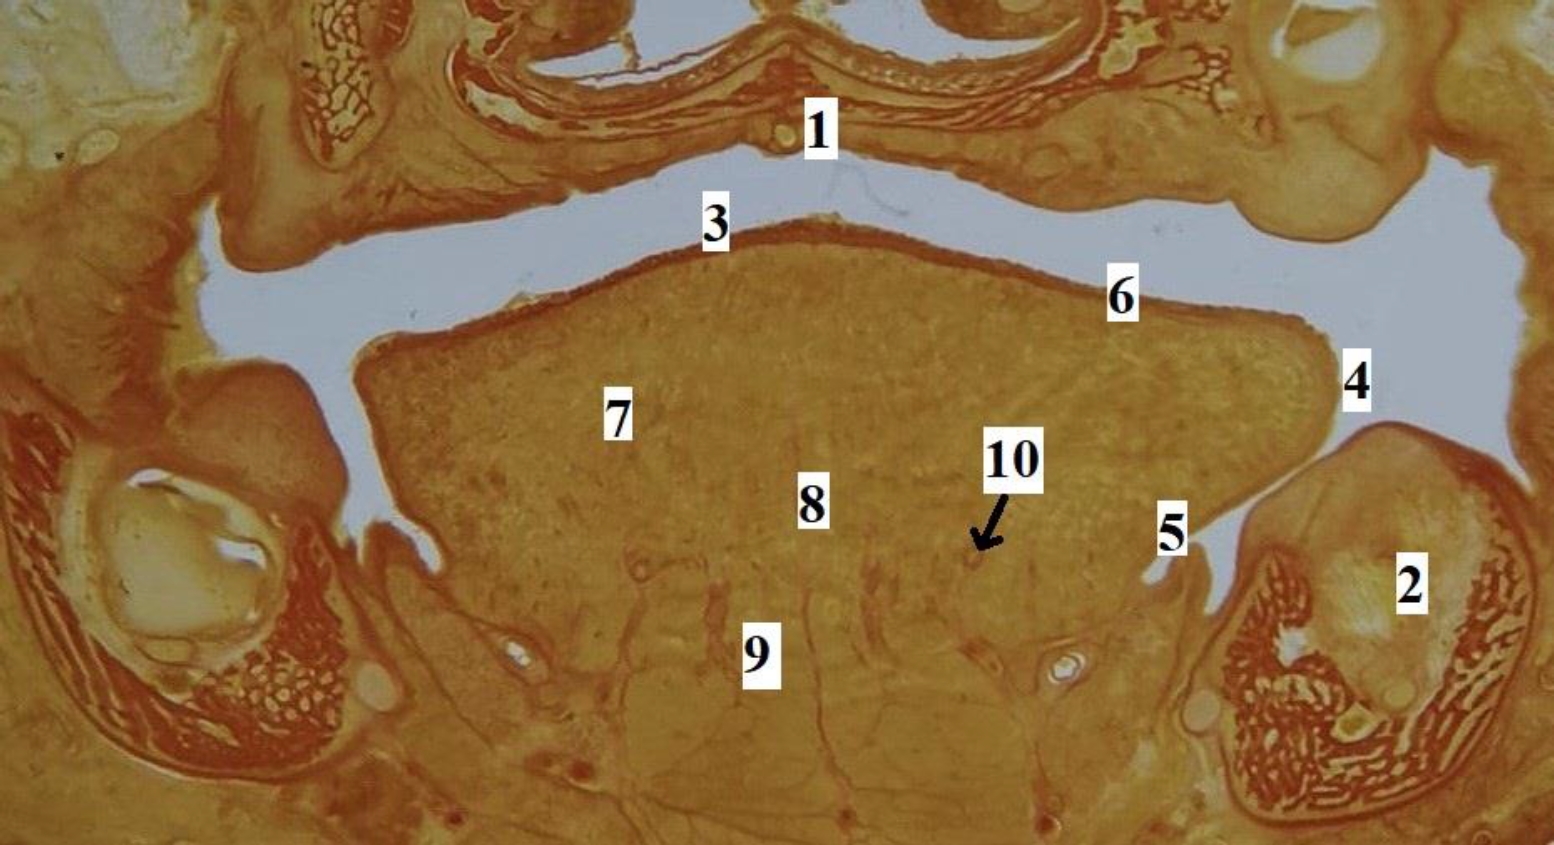

Рис. 2. Макропрепарат языка плода человека. Возраст – 17 недель, пол женский: 1 – слепое отверстие языка; 2 – пограничная борозда языка; 3 – спинка, предбороздовая часть тела языка; 4 – срединная борозда языка; 5 – край языка; 6 – верхушка языка; 7 – желобоватые сосочки языка; 8 – конусовидные, нитевидные, грибовидные сосочки языка

Рис. 3. Язык плода человека. Фронтальная гистотопограмма. Фото под микроскопом MicroOptix MX-1150, ок. ×10, об. 1. Возраст – 22 недели, пол мужской. Окраска по Ван – Гизону: 1 – твердое нёбо; 2 – нижняя челюсть; 3 – спинка языка; 4 – край языка; 5 – эпителий слизистой оболочки нижней поверхности языка; 6 – специализированный эпителий спинки языка; 7 – мышечные волокна поперечной мышцы языка; 8 – перегородка языка; 9 – мышечные волокна подбородочно-язычной мышцы; 10 – глубокая артерия языка